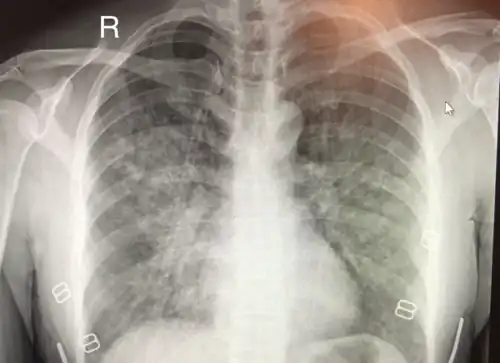

L'œdème pulmonaire de haute altitude (OPHA) est une forme mortelle d'œdème pulmonaire (accumulation de liquide dans les poumons) non cardiogénique qui se produit chez les personnes en bonne santé à des altitudes généralement supérieures à 2 500 mètres[1]. Cependant, des cas ont également été signalés entre 1 500 et 2 500 mètres chez des sujets plus vulnérables.

Le consensus de Lake Louise pour l'œdème pulmonaire en haute altitude a défini des critères largement utilisés pour définir les symptômes de l'OPHA[5]. Après un récent gain d'altitude, la présence de :

- au moins deux symptômes parmi :

- essoufflement au repos,

- toux,

- faiblesse ou diminution de la performance physique,

- oppression thoracique ou congestion ;

- au moins deux signes parmi :

- craquements ou respiration sifflante (pendant la respiration) dans au moins un champ pulmonaire,

- coloration bleue de la peau (cyanose centrale),

- tachypnée (respiration rapide),

- tachycardie (fréquence cardiaque rapide),

- expectoration d'une mousse de couleur saumonée.